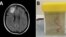

Živi crv pronađen u mozgu pacijentkinje u Australiji